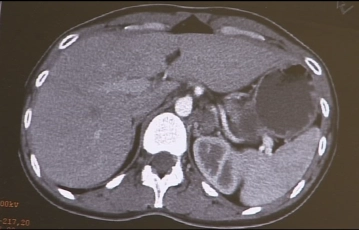

En la imagen se muestra una lesión ocupante de espacio multinodular, de aspecto quístico, de aproximadamente 5-6 cm de tamaño en la región de la glándula suprarrenal izquierda, que clínicamente se identificó como feocromocitoma.

Hallazgo tomográfico computarizado